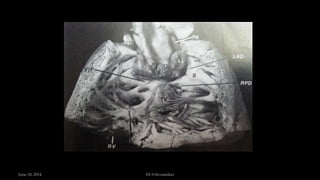

• Single aortopulmonary trunk from base of heart and all 3

circulations arising from it

• Large perimembranous VSD (obligatory) below truncus

• Truncal valve – bi, tri or quadricuspid and often incompetent.

• Pulmonary artery arise in several patterns

• Truncal overriding equally in 60 – 80%, to right in 10-30%, left in 4 –

6%